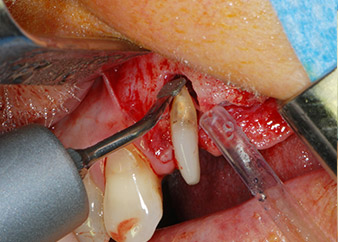

One month later, on the day of surgery, pain and inflammation at tooth 24 were minimal, but mobility of Miller class 2 was still present. After opening the flaps and cleaning the periapical and peri radicular infected tissue, the extent of the bone defect became obvious (Figs. 2 and 3).

At the buccal root, all vestibular and distal bone was missing. Attachment was essentially restricted to the palatal root, underlining the preliminary poor prognosis. Tooth 27 also showed a reduced horizontal attachment and a minimal apical rarefaction (cf. Fig. 1) without clinical symptoms.

However, we maintained our initial plan to retain both teeth as temporary bridge abutments during the six-months osseointegration period of the implants. At reentry, the situation would have to be reassessed. First, in an attempt to manage the endo-perio problem, the remaining root surface was carefully debrided with piezoelectric equipment (Piezomed, W&H, used with the spatula-shaped insert S1, originally designed for erosion of the lateral sinus wall) (Fig. 4).

Then the apex was abraded with the same instrument to remove residual infected apical tissue and to reduce possible accessory root-canal ramifications (apicoectomy) (Fig. 5). A retrograde filling was not necessary because the orthograde filling had just been revised.

Prior to implant placement, infected tissue was removed from the alveolar bone in the implant site and around the abutment teeth with an insert originally designed for bone shaping and collecting bone chips (Piezomed, insert B5) (Figs. 6 and 7).